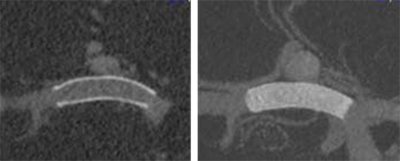

Un marcador radiopaco marca el "punto de no retorno" hasta el cual el p64 MW puede reenvainarse en el microcatéter.

La aposición óptima de la pared del vaso puede evaluarse más fácilmente por el p64 MW totalmente visible, lo que resulta en un posicionamiento más preciso.